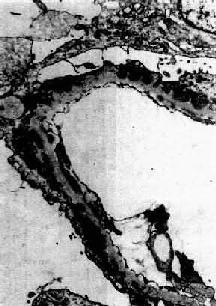

图12-18 膜性肾小球肾炎 电镜下见肾小球毛细血管基底膜表面,上皮细胞下电子致密沉积物,基底膜向表面突出伸入沉积物之间,上皮细胞足突融合